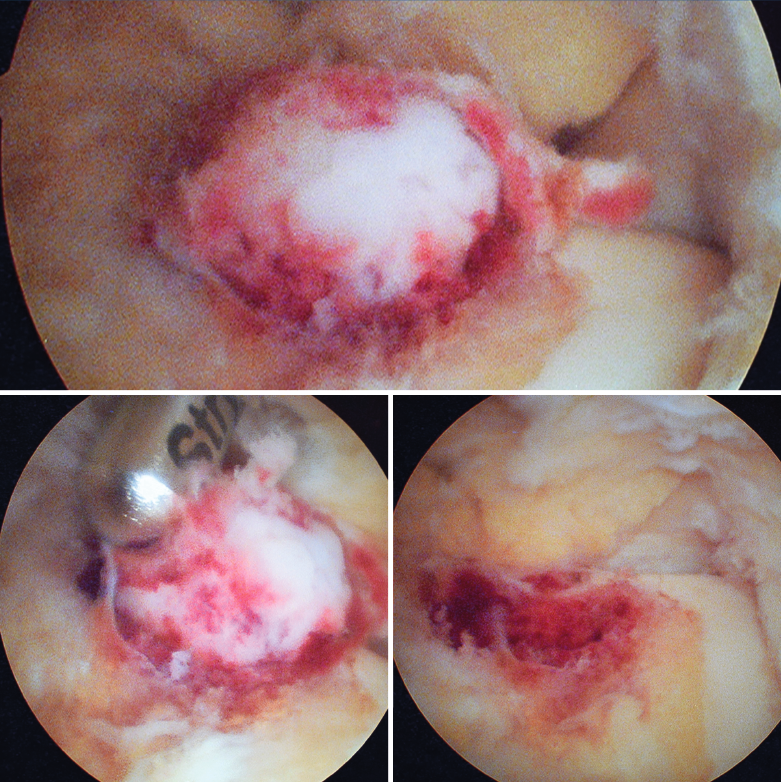

Figura 4. Mediante los portales artroscópicos anteriores habituales (anteromedial y anterolateral) se observa a nivel del cuello del astrágalo anterointerno la característica tumoración de color rojo cereza, que se desbridó con sinoviotomo.

Se visualizó la cúpula astragalina y se observó a nivel del cuello del astrágalo anterointerno una tumoración rojiza con intensa reacción sinovial; se desbridó mediante un sinoviotomo de 4,5 mm (Stryker®, Kalamazoo, Michigan) (Figura 4), tras lo cual se comprobó la inestabilidad de la lesión que se desprendió en bloque (Figura 5), remitiéndose a estudio anatomopatológico.

La escisión artroscópica es una opción de tratamiento que ha resultado efectiva en las lesiones periarticulares, pudiendo observar una elevación de color rojo cereza, tal como se describe en la literatura(22,25,26), y permitiendo una resección segura y limitada de la lesión(27,28), posibilitándonos el estudio anatomopatológico de la muestra, a diferencia de las técnicas guiadas por TAC o RMN. Si es necesario, podemos ayudarnos de la fluoroscopia intraoperatoria(29).